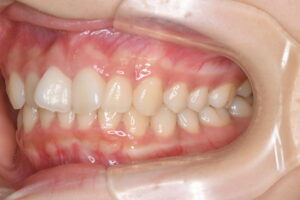

▼治療後の口腔内写真1

▼治療後の口腔内写真2